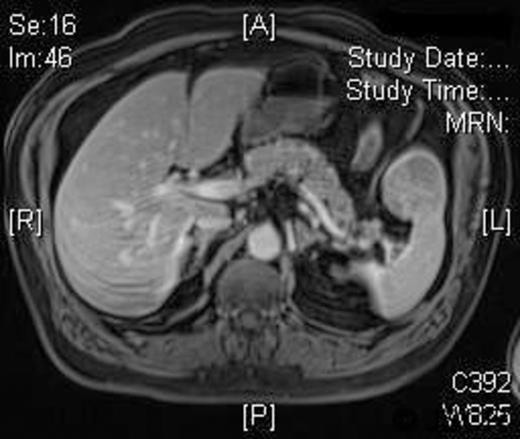

The operative time was 50 minutes and the blood loss was less than 20 ml. The patient made an uneventful recovery and was discharged on the second postoperative day. Histology demonstrated complete excision of a LCA with no cell atypia. A 3-month postoperative MRI showed no disease recurrence and normal appearance of the splenic remnant [Figure 3].